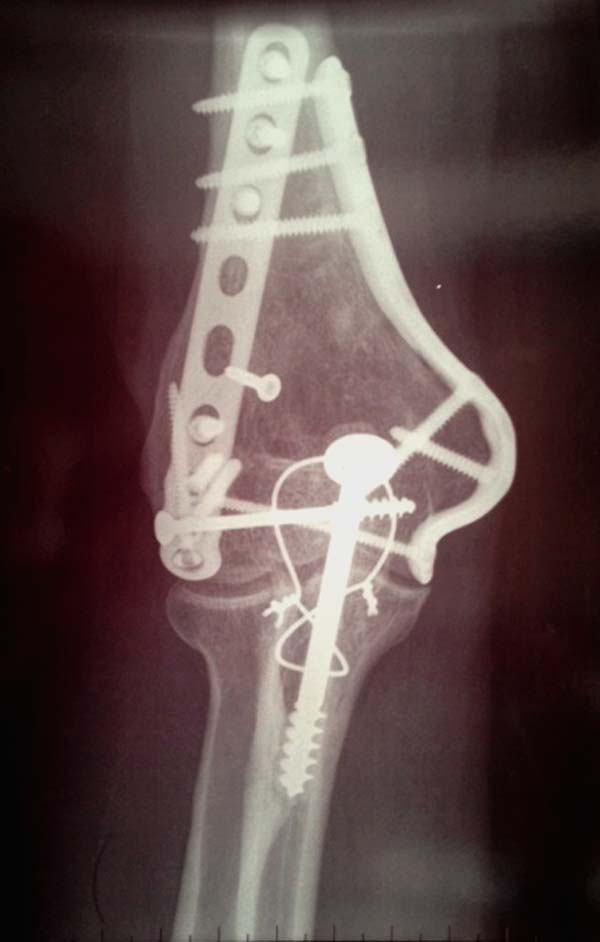

Разработаны различные концепции установки пластин на дистальное плечо:

две параллельные в 180 или под углом в 90 градусов. Почти все компании

имеют все варианты пластинок, а Acumed признает так называемую Keystone

concept  http://www.acumed.net/distal-humerus-plates

Примеры: первому более 15 лет фиксирован шурупом и tension band

technique, а второй перелом открытый больной 80 лет, после наружного

фиксатора в первом этапе и окончательная фиксация вторично. Третьий раз

внесуставная остеотомия...